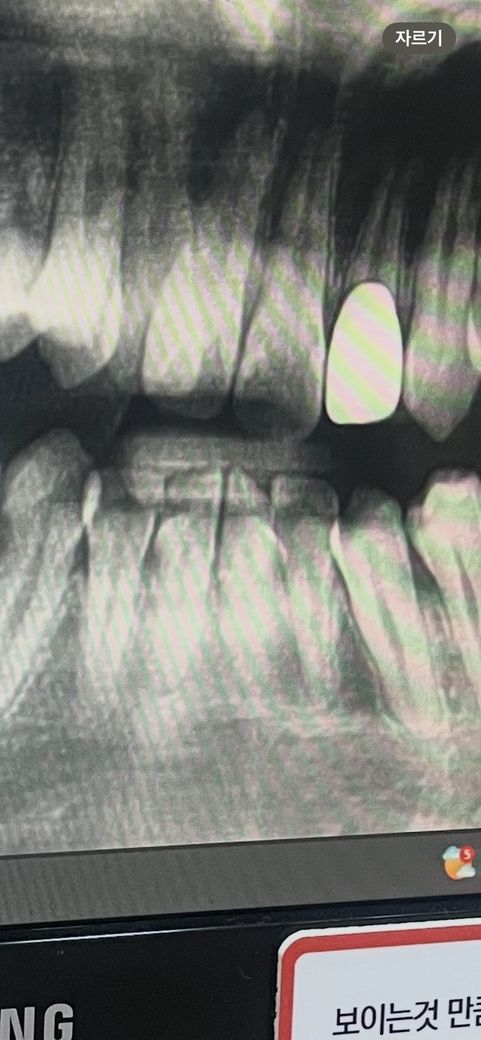

앞니 뿌리 염증인가요 약간의 증상있으나 심한정도는 아닙니다

이거 치아뿌리 염증인가요? ㅠㅠ

*사진은 9개월전 교정하기 전 입니다.

현재 치아 교정중인 사람인데요 앞니가 평소에는 괜찮다가 스프링붙이고 공간벌리기 끝나고 스프링 떼고 난 후에 압력? 약간의 시큰거림(특히 양치 후)이 있습니다 그리고 해당앞니는 예전부터 초기충치가 있던 치아이구요 초기충치 발견당시(9개월전)에 신경을 계속 쓰니까 증상이 있다가 신경안쓰니까 사라졌다가 최근에 증상이 조금 있어요 교정때문인지 충치 때문인지.. 또 치과를 몇군데 갔었는데 초기충치를 다들 잘 발견 못 했고 짚어줘야 알았습니다 문제 있는 치아인가요? 신경치료,발치 등 해야하나요?

사진으로 보이는 충치만으로는 치근단 질환이 생길 정도는 아닌 것으로 보입니다. 방사선상 어두운 부분이 보이긴 하나 치근단 질환을 확인하기 위해서는 CT 촬영 등에 정밀한 검사가 필요할 수 있습니다.

엑스레이 사진 순서에 있어서 젤 왼쪽이 가장 최근이라면 염증이 잡히고 있는 상태라고 볼 수 있겠으나 파노라마 사진 말고 치근단 사진이 좀 더 정확합니다